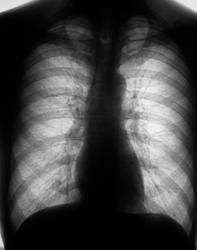

Пациент в 2007, 2008 гг. проходил профилактическую флюорографию - иллюстрации ниже. При прохождении флюорографиив 2009 г. "картинка" резко отличается от предыдущих.

1.Флюорограммы за 2007, 2008 гг. представлены, оценены, как норма.